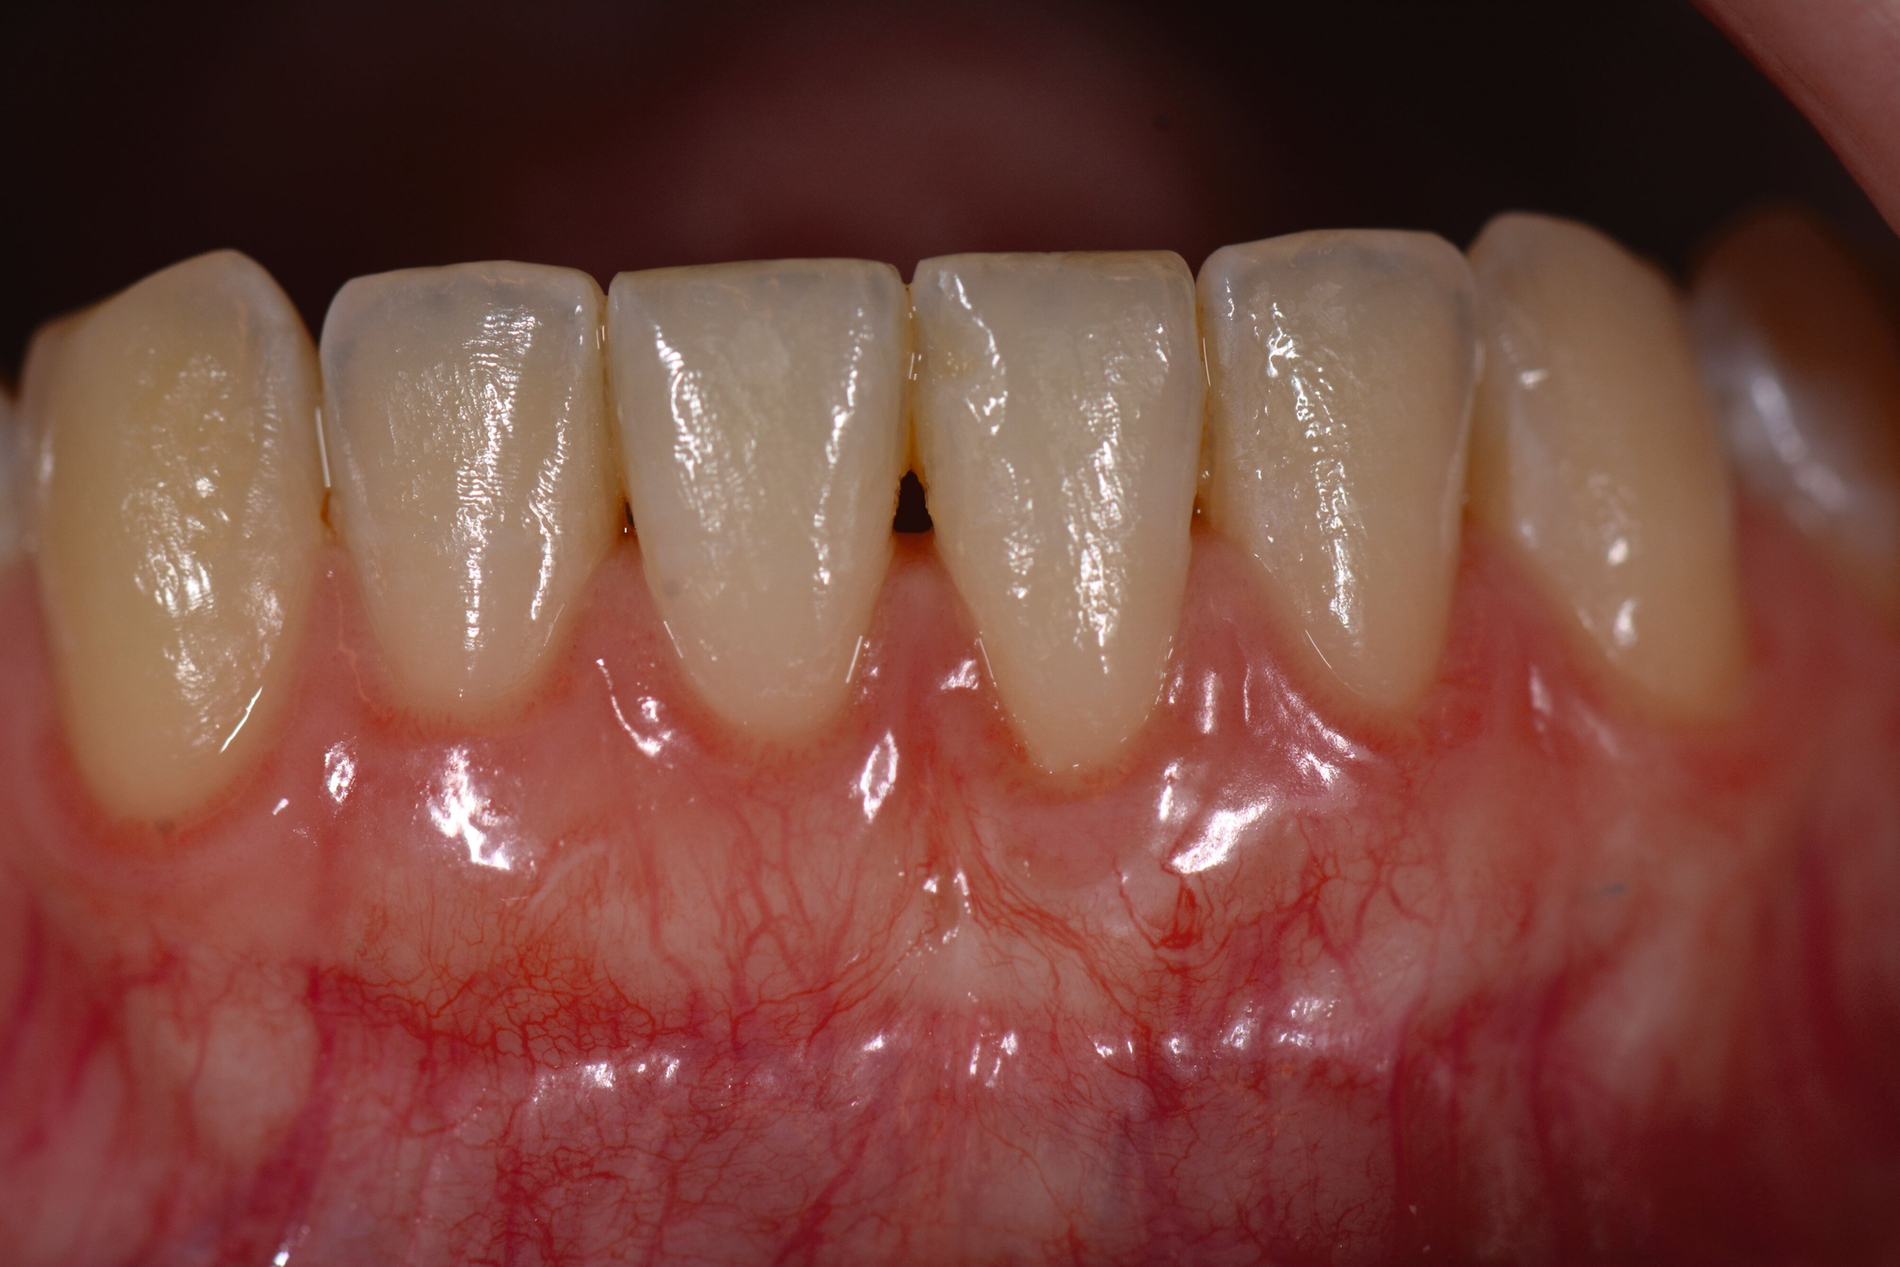

Das „klassische“ BGT wurde bereits in den 1970er-Jahren beschrieben und ist besonders verbreitet bei der Behandlung von gingivalen Rezessionen und der Weichgewebsaugmentation um Implantate. Das Transplantat wird durch eine sorgfältige Präparation unterhalb des Epithels vom lateralen und eher anterioren Gaumen gewonnen. Durch den Erhalt des bedeckenden Gewebes soll eine primäre Heilung sichergestellt werden. Die Höhe des Gaumendachs und somit die Entfernung zur Arteria palatina sowie die Dicke der Schleimhaut, vor allem über den palatinalen Wurzeln der Molaren zusammen mit den Rugae des anterioren Gaumens, sind die limitierenden Faktoren bei dieser Technik.

Trotz des Verbleibs des Epithels kann es zu sekundärer Wundheilung mit entsprechender Morbidität postoperativ kommen, besonders bei Techniken, die mehrere Inzisionen beinhalten, wie den sogenannten Trap-Door-Techniken, so dass sich die „Single-Incision-Technik“ durchgesetzt hat [Fickl et al., 2014]. Gegen eine übermäßige Blutung und postoperative Morbidität empfiehlt sich klinisch die routinemäßige Anwendung einer Verbandplatte, entweder in der Tiefziehtechnik oder präoperativ mittels eines Thermoplasts, so dass sich früh ein stabiles Blutkoagel bildet und die Wundheilung an der Entnahmestelle ungestört ablaufen kann. Dadurch wird die Morbidität klinisch deutlich reduziert. Das sBGT zeigt ästhetisch sehr gute Ergebnisse mit Blick auf Oberflächenstruktur sowie Farbe und kann unter anderem im Rahmen der Envelope- oder Tunneltechnik oder auch über einer Extraktionsalveole bewusst exponiert belassen werden, um zusätzlich befestigte Gingiva zu gewinnen.

Die Wundheilung nach dieser Technik erfolgt anders als beim sBGT immer sekundär, somit wurden bei Vergleichsstudien eine signifikant erhöhte Morbidität, Schwellungen und ein erhöhtes Nachblutungsrisiko beschrieben [Del Pizzo et al., 2002; Griffin et al., 2006], was jedoch bei entsprechender Versorgung des Gaumens umgegangen werden kann [Zucchelli et al., 2010]. Die Versorgung der Spenderregion kann mit Kollagenvlies, Cyanoacrylatkleber, Verbandplatte oder einer Kombination erfolgen. Dies kann die Morbidität deutlich reduzieren [Tavelli et al., 2019b]. Ein Vorteil von dBGT ist die Stabilität der Gewebedicke im Laufe der Zeit, was im Gegensatz zur beschriebenen Schrumpfung von sBGT steht, die häufig beobachtet wird [Zucchelli et al., 2018].

Eine Übersichtsarbeit, die sBGT und dBGT im Rahmen der Rezessionsdeckung verglich, empfahl primär die Anwendung des dBGT. So lag die mittlere Wurzelabdeckung nach zwölf Monaten mit dem sBGT bei 89,3 Prozent im Vergleich zu 94 Prozent beim dBGT. Die Daten der dBGT-Gruppe stützten sich jedoch nur auf die Ergebnisse einer einzigen Arbeitsgruppe und die Gruppen mit der höchsten durchschnittlichen Wurzeldeckung wurden für das sBGT berichtet, so dass hier ein gewisser Centereffekt vermutet werden kann. Weiterhin besteht bei dBGT ein gewisses Risiko für ästhetische Komplikationen wie eine keloidartige Narbenbildung, eine unnatürliche Randsituation oder eine deutlich hellere und glattere Oberfläche, wenn das Transplantat nicht korrekt gehandhabt wird, der Decklappen sehr dünn ist oder das Transplantat offen einheilt [Gluckman et al., 2019; Zucchelli et al., 2014b].